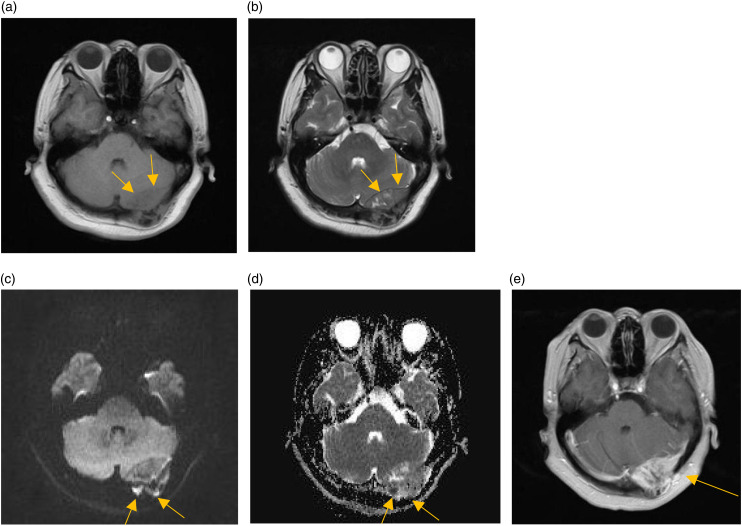

Osteosarcomas predominantly manifest in the long bones of the extremities, with rare occurrences in the skull. A case involving of a 53-year-old female who presented to the authors' hospital for examination due to dizziness was incidentally found to have an occipital bone mass, which was initially diagnosed as a benign tumor and did not receive sufficient attention. Two years later, owing to tumor enlargement, the patient underwent further evaluation at the same institution, which revealed evidence of occipital bone destruction. Pathological analysis confirmed the diagnosis of osteosarcoma. The patient underwent surgical resection followed by radiotherapy. Despite its infrequency and uncharacteristic initial presentation, skull osteosarcomas should not be overlooked.